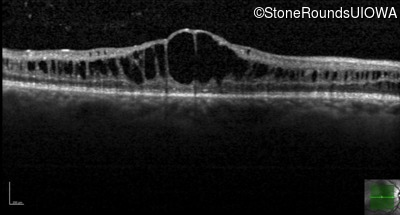

Optical Coherence Tomography - Left - 20/40

Exemplar / OCT Stack

OCT Stack